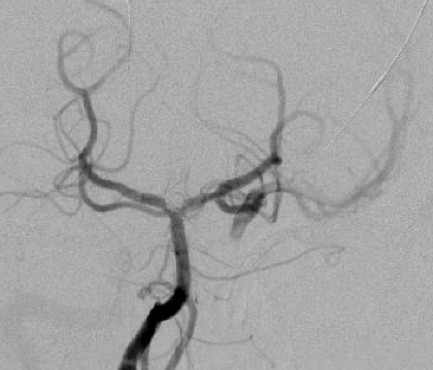

最终脑血管造影示所有分支血流通畅,动脉瘤无显影。